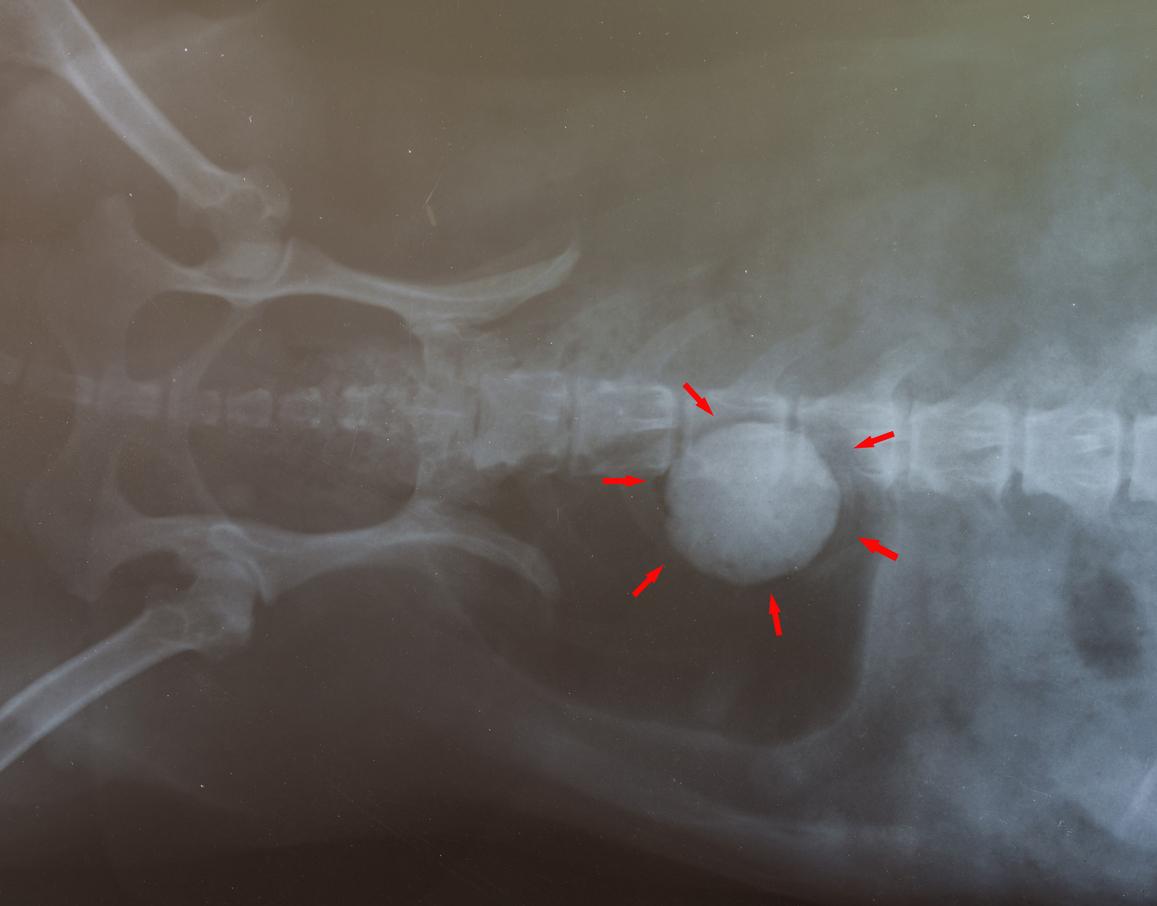

A pesar de que se han extendido por la red algunos consejos caseros para hacer que tu perro expulse las piedras que ha comido como, por ejemplo, provocar el vómito, lo más recomendable y más sano para la salud de tu mascota es que lo lleves de inmediato al veterinario para que valore y te recomiende el mejor procedimiento. A través de exámenes y radiografías se podrá determinar el lugar en el que está la piedra y cuál es la mejor manera de intervenir para no dañar sus órganos.

Puede ser que indique provocar el vómito o, por el contrario, quizás sea necesaria una cirugía. No obstante, ello dependerá de factores como el tamaño de la piedra, la cantidad de piedras, dónde se encuentran dentro del aparto digestivo del can, la salud general de este, etc.